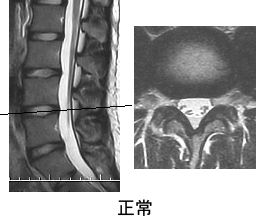

MRI検査・脊髄造影検査・CT検査

腰部脊柱管狭窄症が疑われた場合、MRI検査を行います。

更に詳しい検査が必要な場合は、脊髄造影・CTなどを行います。